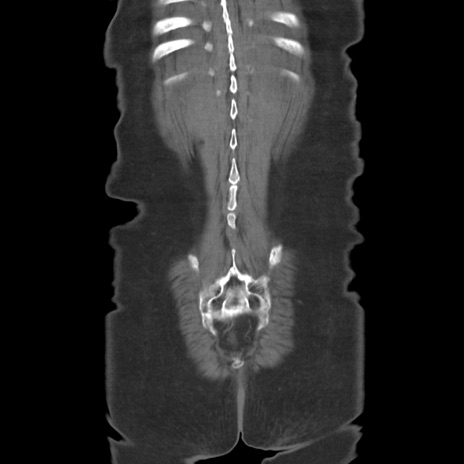

症例19(冠状断像)

【症例】80歳代女性

【主訴】下腹部痛

【現病歴】約8時間前より下腹部痛の出現あり、救急外来受診。

【既往歴】両側付属器切除

【身体所見】意識清明、下腹部正中に手術痕あり、その部位に一致して圧痛と反跳痛あり。腸蠕動音は亢進。

【データ】WBC 9300、CRP 0.15